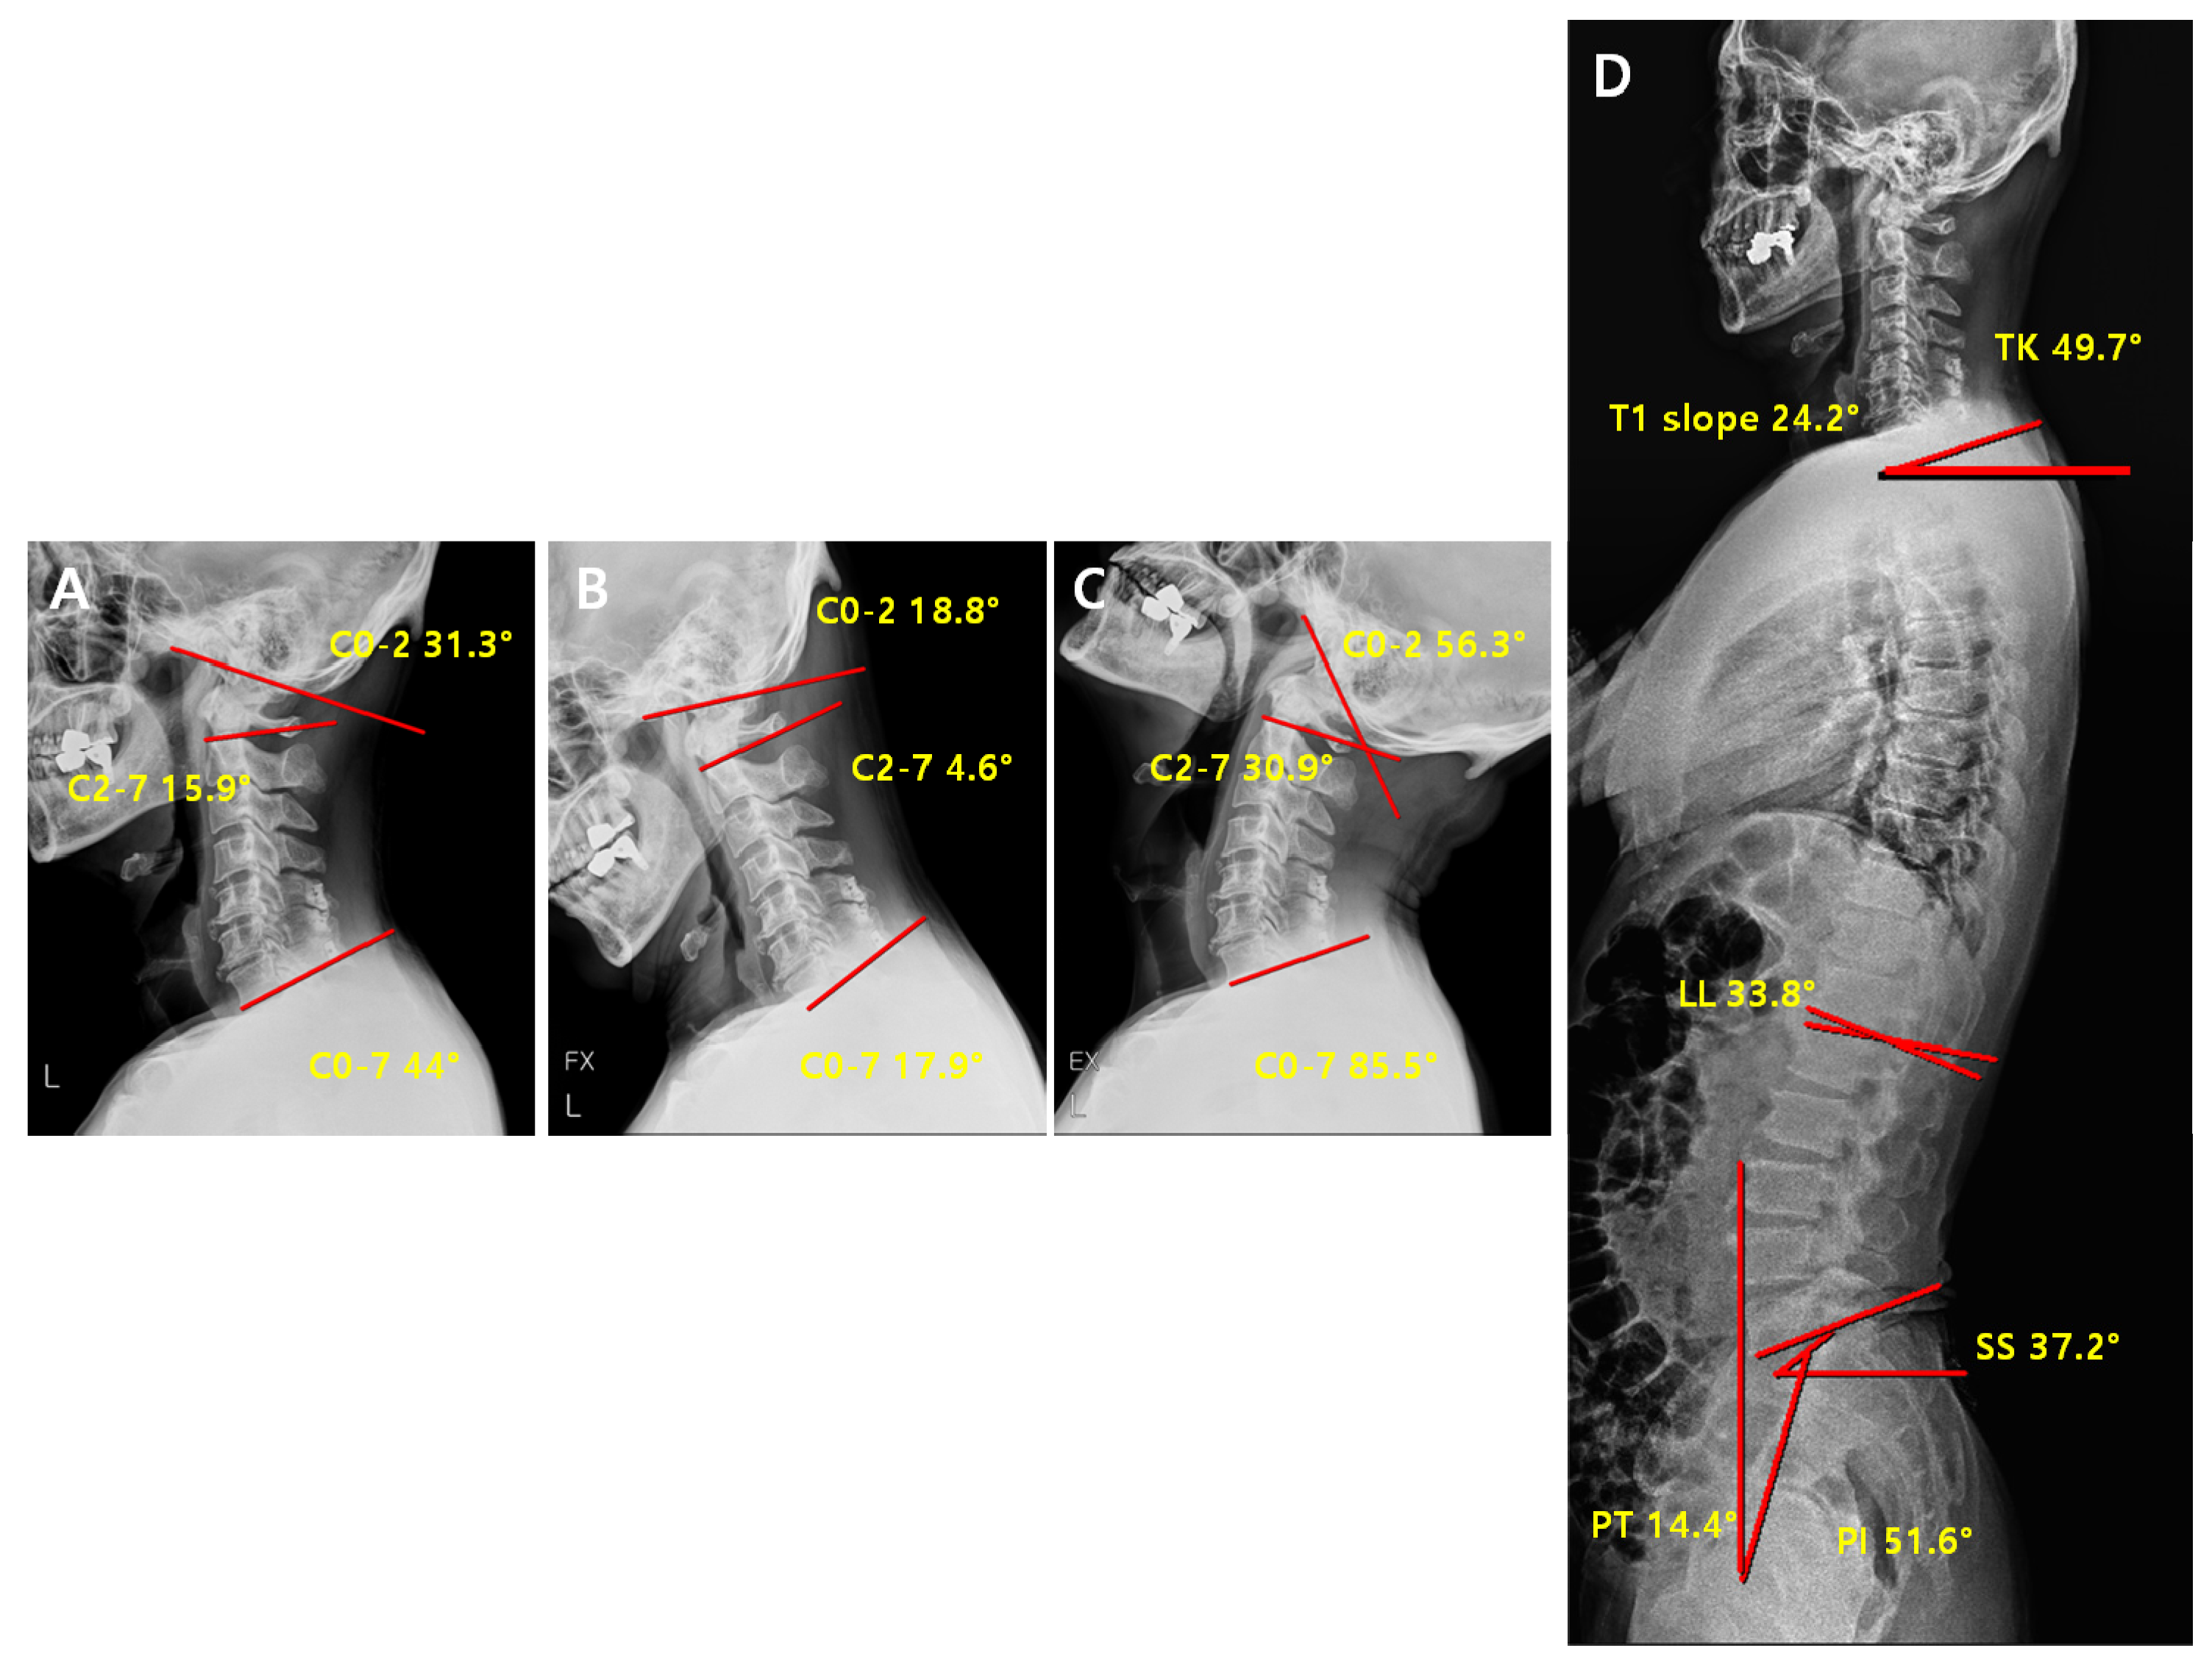

2.3. Radiographic Measurement

2.4. Radiological Analysis